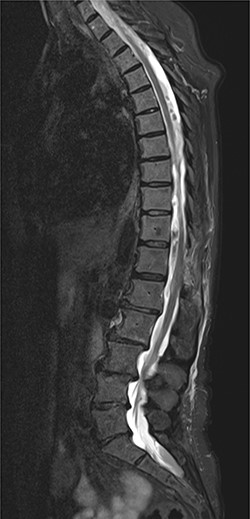

On 17 February 2020, she underwent TKA (Fig. 1). Spinal anesthesia was performed, with the patient in sitting position with one laborious puncture, as referred by the anesthesiologist. The patient received low molecular weight heparin (4000 UI enoxaparin sodium) subcutaneously 12 h after the surgery and a second shot dose 24 h later. On the second post-operative day (19 February 2020), early in the morning, the patient complained of numbness in her lower extremities and low back pain, partially relieved with analgesics. Four hours later, she was complaining for severe difficulty in moving her legs with increased low back pain. The physical examination showed flaccidly paralyzed left lower leg (0/5 left quadriceps, 0/5 left extensor digitorum longus, 0/5 left tibialis anterior and 0/5 left extensor hallucis longus), marked motor function reduction of the right lower leg (1/5 right quadriceps, 2/5 right extensor digitorum longus, 2/5 right tibialis anterior and 2/5 right extensor hallucis longus), sensory loss in both lower limbs, Babinski sign negative bilaterally and preserved sphincter functions. Magnetic resonance imaging (MRI) was required to rule out an acute spinal compression. The images showed a spindle-like mass, mostly intradural, from T11 to L3, hypointense in T2 and heterogeneous in T1 images compressing the dural sac (Fig. 2). Therefore, a diagnosis of acute spinal hematoma was made, and the patient was transferred to the Neurosurgery Department, and surgical decompression was scheduled. A bulky blood clot was removed through a spino-hemilaminectomy of T11 and T12 followed by a posterior dural incision. The source of bleeding was identified in a perimedullary vein on the dorsal surface of the spinal cord that was coagulated. Surgery was performed 3 h after diagnosis, and few hours later, the patient was able to perform a flexion-extension of both lower limbs. She was able to start walking with a walker 24 h later. A low molecular weight heparin (2000 UI Enoxaparin sodium) subcutaneously was started 1 week after surgical decompression. This dosage was increased to 4000 UI 2 days later. On 24 February 2020, a follow-up MRI was performed, and it showed a partial resolution of the hematoma with a confined area of myelopathy at the T12 level (Fig. 3). On the 26 February 2020, the patient started the rehabilitation protocol with the gradual improvement of the neurological status.

Follow-up MRI; it demonstrates a partial resolution of the hematoma with a confined area of myelopathy at the T12 level.